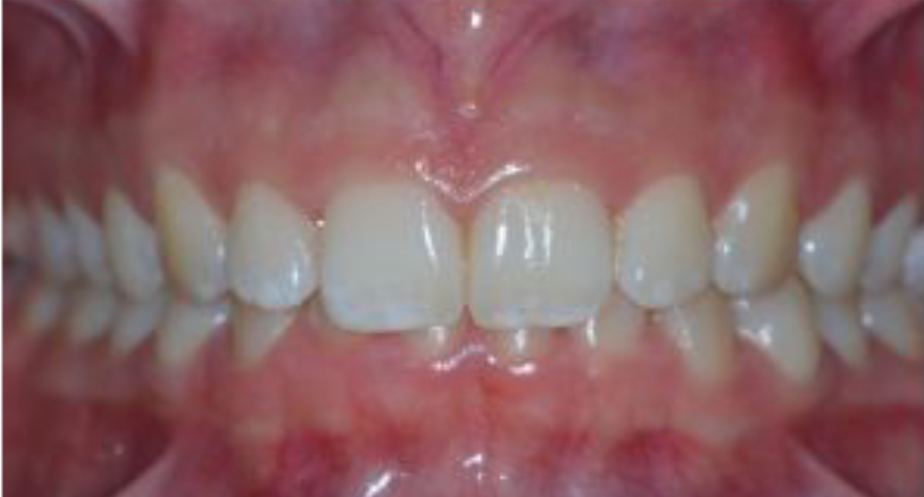

Sorriso Gengival

Sorriso Gengival é caracterizado por uma excessiva exposição da gengival superior no momento da realização de um sorriso. Normalmente, não traz danos à saúde. O problema está na aceitação individual e pessoal de um possível desconforto estético causado pela ausência de harmonia e simetria facial.

O grau de exposição (quantidade) gengival varia de pessoa para pessoa consequentemente a solução deve ser adequada à cada caso, podendo ir de uma simples aplicação de toxina botulínica passando cirurgia plásticas periodontais simples à complexas.

Uma avaliação criteriosa deve ser realizada pelo periodontista, para tanto podem ser utilizados exames radiográficos, tomográficos e fotográficos. Desta forma, o profissional terá como definir a melhor forma de intervenção.